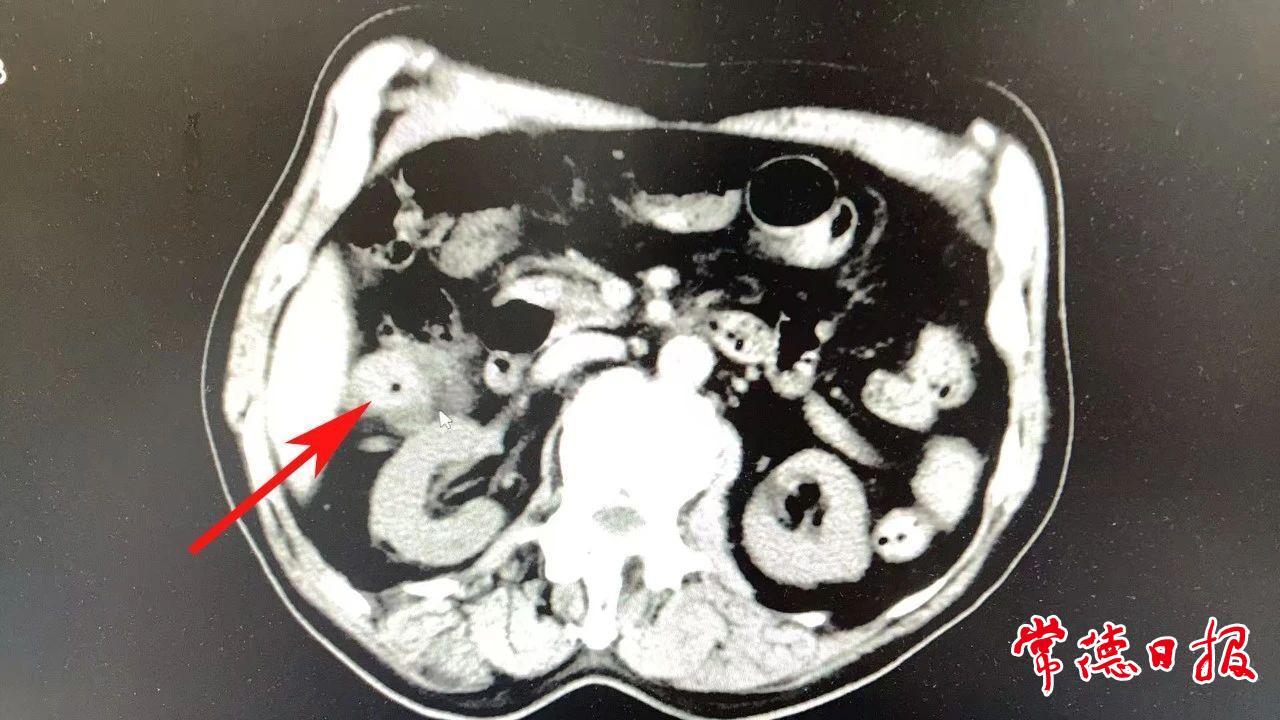

此次,患者被確診升結(jié)腸癌后,前往常德市第一中醫(yī)醫(yī)院胃腸、疝、小兒外科團(tuán)隊尋求治療。結(jié)合患者三次發(fā)生在不同部位的結(jié)腸癌變、既往兩次大型手術(shù)史疊加76歲高齡帶來的心肺功能衰退,讓患者的病情異常復(fù)雜。“醫(yī)生,我這把年紀(jì)還能做第三次手術(shù)嗎?”面對李爺爺?shù)脑儐枺剖裔t(yī)療團(tuán)隊經(jīng)過周密評估,提出了兩種手術(shù)方案:相對安全的回腸造口術(shù),或風(fēng)險更高但能顯著提升生活質(zhì)量的開腹右半結(jié)腸癌根治術(shù)。前者雖風(fēng)險較小,但術(shù)后將形成兩個造口,嚴(yán)重影響生活質(zhì)量;后者能保留部分結(jié)腸,維持腸道菌群平衡、增強(qiáng)免疫力,是改善術(shù)后生存質(zhì)量的最佳選擇。然而,該方案要求在根治性切除腫瘤的同時,必須精準(zhǔn)保留橫結(jié)腸中動脈左支,否則極易導(dǎo)致剩余腸管壞死,手術(shù)難度陡增,且一旦出現(xiàn)吻合口瘺等并發(fā)癥,將直接危及生命。

經(jīng)過嚴(yán)謹(jǐn)?shù)亩鄬W(xué)科討論,團(tuán)隊最終選擇迎難而上,決定實施風(fēng)險較高但能顯著提高生活質(zhì)量的“開腹右半結(jié)腸癌根治術(shù)”。該手術(shù)需要在徹底切除腫瘤的同時,精準(zhǔn)保留橫結(jié)腸中動脈左支,技術(shù)要求極高。手術(shù)過程中,科室副主任、主任醫(yī)師任軍華帶領(lǐng)團(tuán)隊運用“膜解剖精準(zhǔn)分離技術(shù)”,在嚴(yán)重腹腔粘連的情況下,耗時3小時順利完成手術(shù),出血量僅50ml。術(shù)后,醫(yī)護(hù)團(tuán)隊為患者制定了包括中醫(yī)調(diào)理在內(nèi)的個性化康復(fù)方案,李爺爺恢復(fù)良好,術(shù)后第7天即康復(fù)出院。